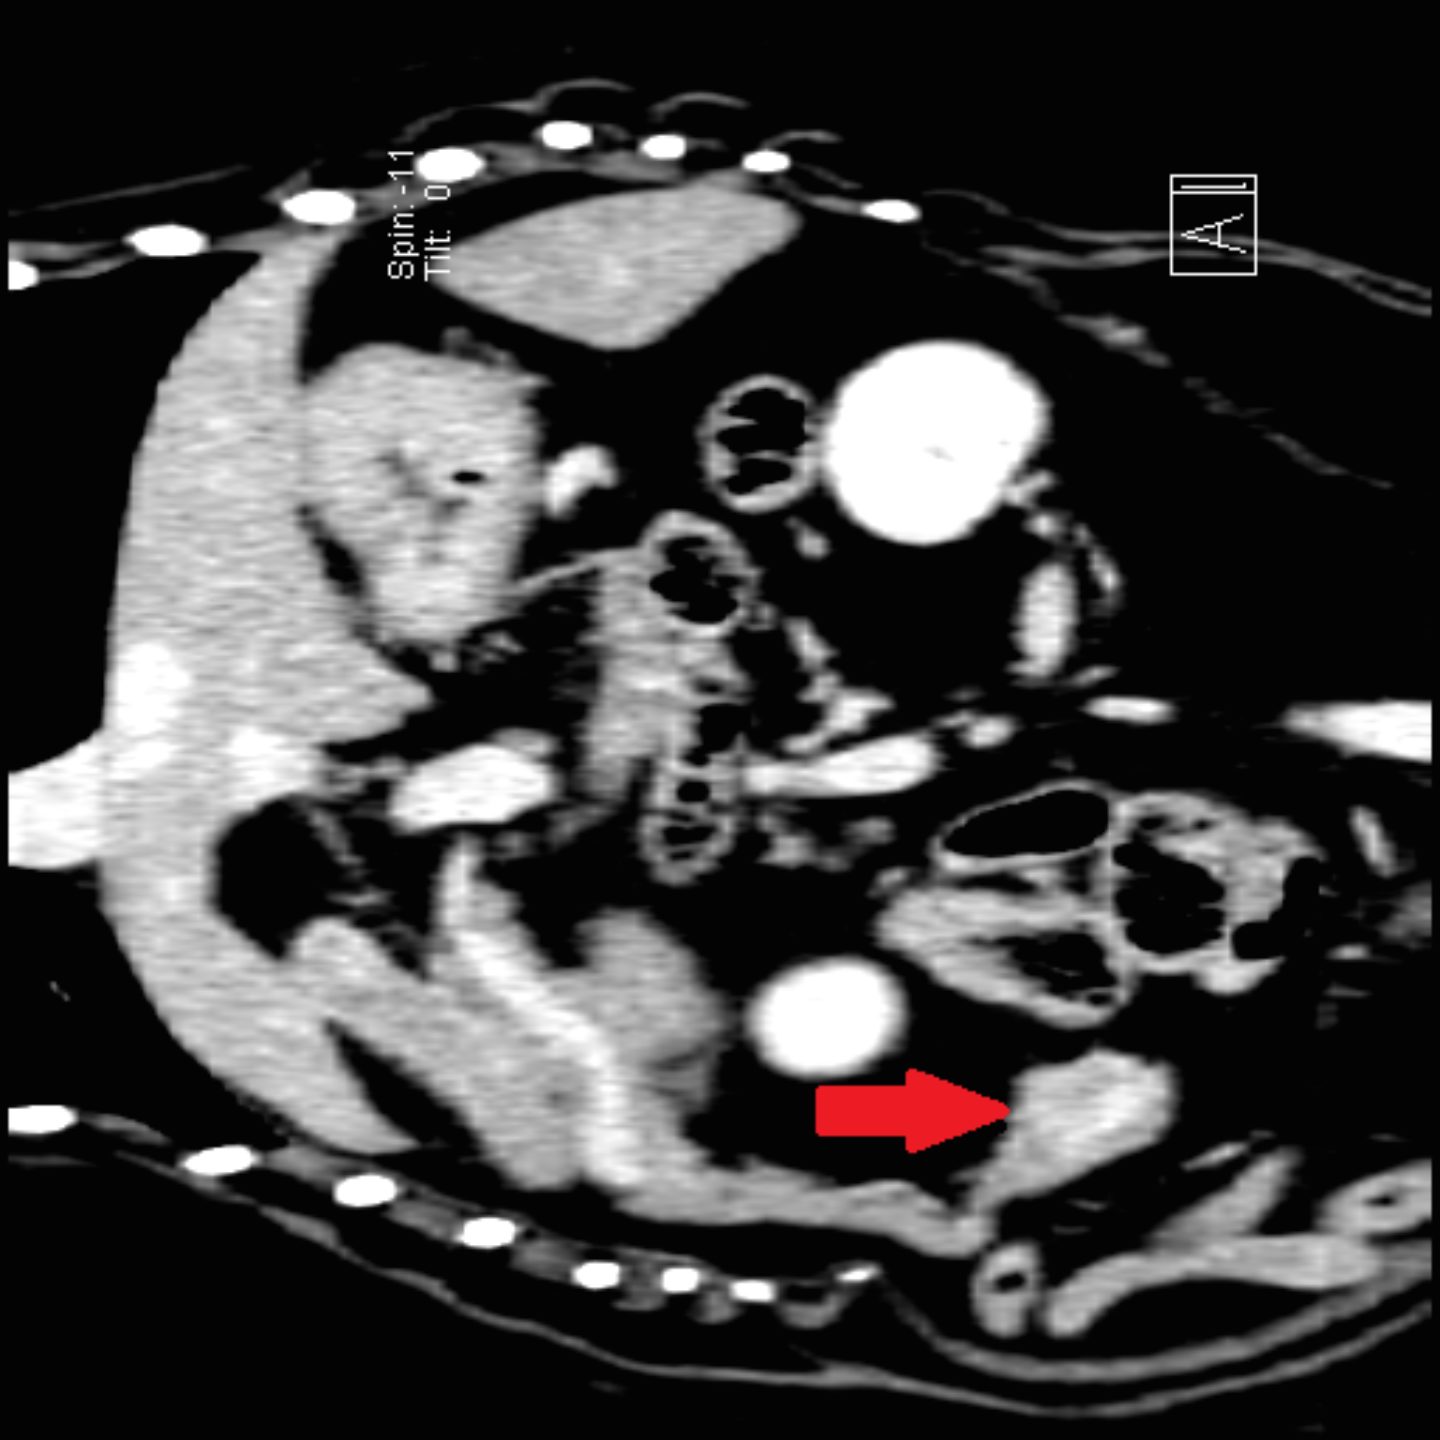

Da Ronja trotz der Kortisontherapie immer wieder Episoden von Schwäche zeigte, galt es nun zügig zu einer Therapieentscheidung zu kommen. Die Computertomographie mit ihrer gegenüber dem Röntgen und Ultraschall deutlich verbesserten Darstellung von Gewebegrenzen ist hier die Methode der Wahl. Ein entscheidender Vorteil ist auch, dass mittels geeigneter Kontrastmittel die Darstellung und Abgrenzung von bösartigen Tumoren möglich ist. Insbesondere lässt sich mit der Computertomographie eine etwaige Streuung der Insulinome mit hoher Zuverlässigkeit abklären.

Tumor im Bereich der Bauchspeicheldrüse. Das Ergebnis der Computertomographie von Ronja zeigte tatsächlich im verdächtigen Bereich der Bauchspeicheldrüse einen Tumor, der nach einer Kontrastmittelgabe deutlich zu erkennen war. Weder in der Brusthöhle noch in der Bauchhöhle waren Metastasen nachzuweisen, was bedeutete, dass das Insulinom noch nicht gestreut hatte. In einem ausführlichen Gespräch wurden die Chancen und die Risiken einer Operation im Detail mit Ronjas Besitzerin besprochen. Bereits zwei Tage später konnte Ronja operiert werden. Bei der Operation wurde Ronja der Teil der Bauchspeicheldrüse entfernt, in dem sich der Tumor befand. Nach der erfolgreichen Operation war ihr Blutzucker innerhalb von kurzer Zeit im Normalbereich. Schon am nächsten Morgen empfing sie ihr Frauchen schwanzwedelnd, als diese zu Besuch kam und zeigte keinerlei Schwäche oder Kollabieren mehr. Bei den folgenden Kontrollen im Laufe des Tages war der Blutzucker weiterhin im Normalbereich, Ronja war beim Gassigehen überaus munter und wir entschieden uns, sie bereits am Abend nach Hause zu entlassen. Bereits in den nächsten Tagen konnte sie ihre alten Gewohnheiten wie zum Beispiel lange Spaziergänge wieder aufnehmen.